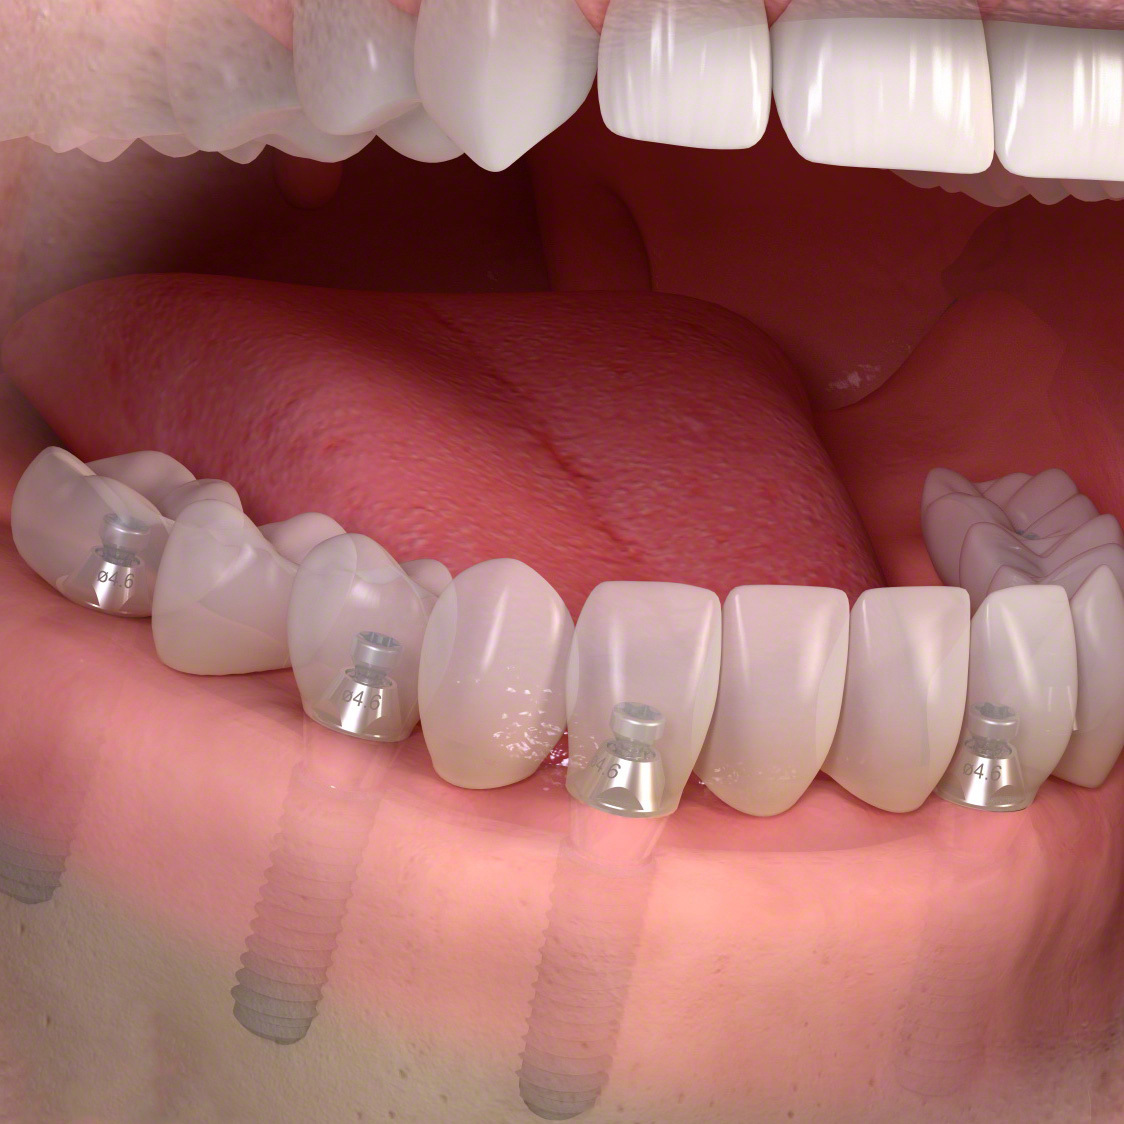

インプラント(多数歯欠損ケース)

インプラントブリッジタイプ

・インプラントとインプラントでブリッジが可能です。

数本の歯を失った。

手術でインプラントを埋める。

インプラントに土台を接続します。

ブリッジタイプの被せ物を装着します。

多くの歯を失ったケース

固定式タイプ

・5~8本のインプラントによって自分の歯のように噛めるよう修復

多くの歯を失った場合。

人工歯を装着します。

インプラント治療で修復。